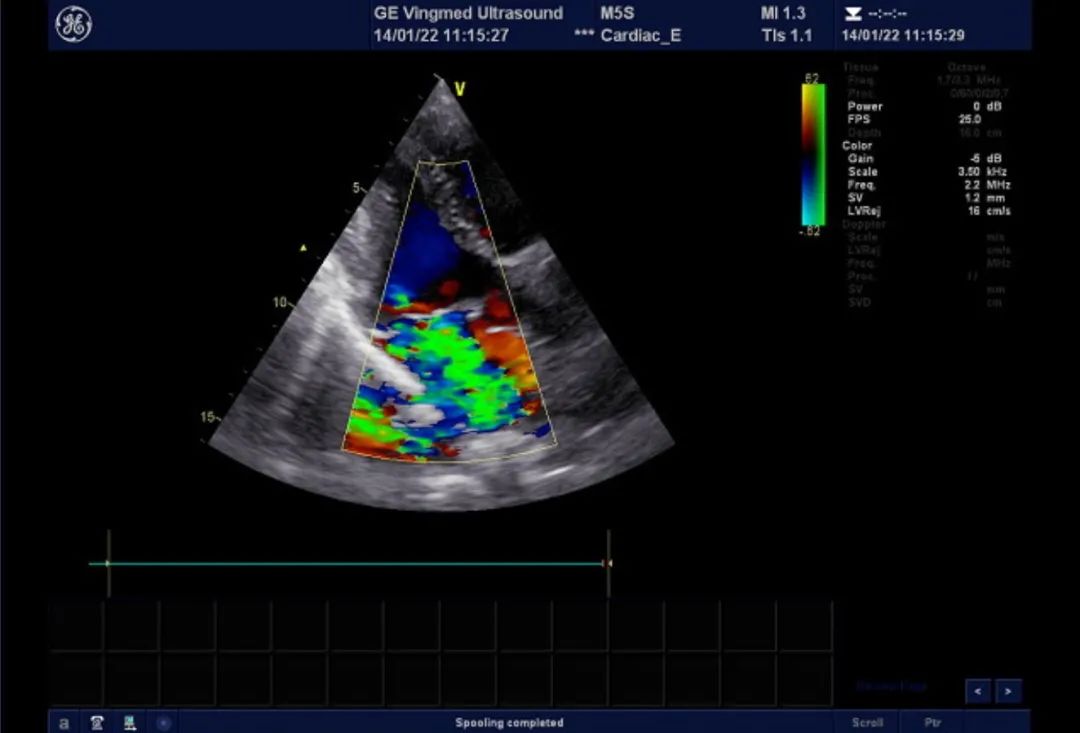

二尖瓣后叶脱垂,大量返流

术中食道超声提示二尖瓣瓣叶冗长,组织增厚,多处返流。提示barlow综合征可能。

术中探查二尖瓣叶过长,瓣叶过长部分常稍增厚、起皱,呈苍白色。术中盐水注水检查发现P2、A2、P3、C2区多处返流。证实患者为barlow综合征。

术中食道超声监测

术中超声检测提示二尖瓣瓣叶对合良好,瓣叶对合高度1cm,未见明显返流。房间隔缺损修补术后,未见残余漏。术中及术后未出现相关并发症,手术圆满完成。患者已脱机拔管,转回普通病房,拟年前出院。